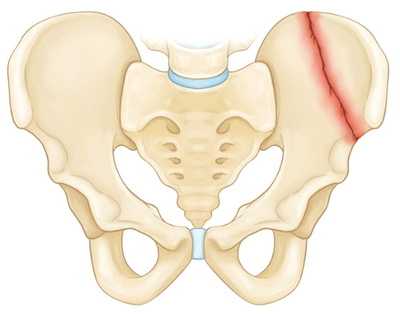

На рисунке — перелом крыла подвздошной кости

Стабильные переломы. Данный тип переломов обычно отличается наличием лишь одной линии перелома и сохранением анатомии тазового кольца. Низкоэнергетические переломы — это обычно стабильные повреждения. К стабильным переломам относятся следующие: